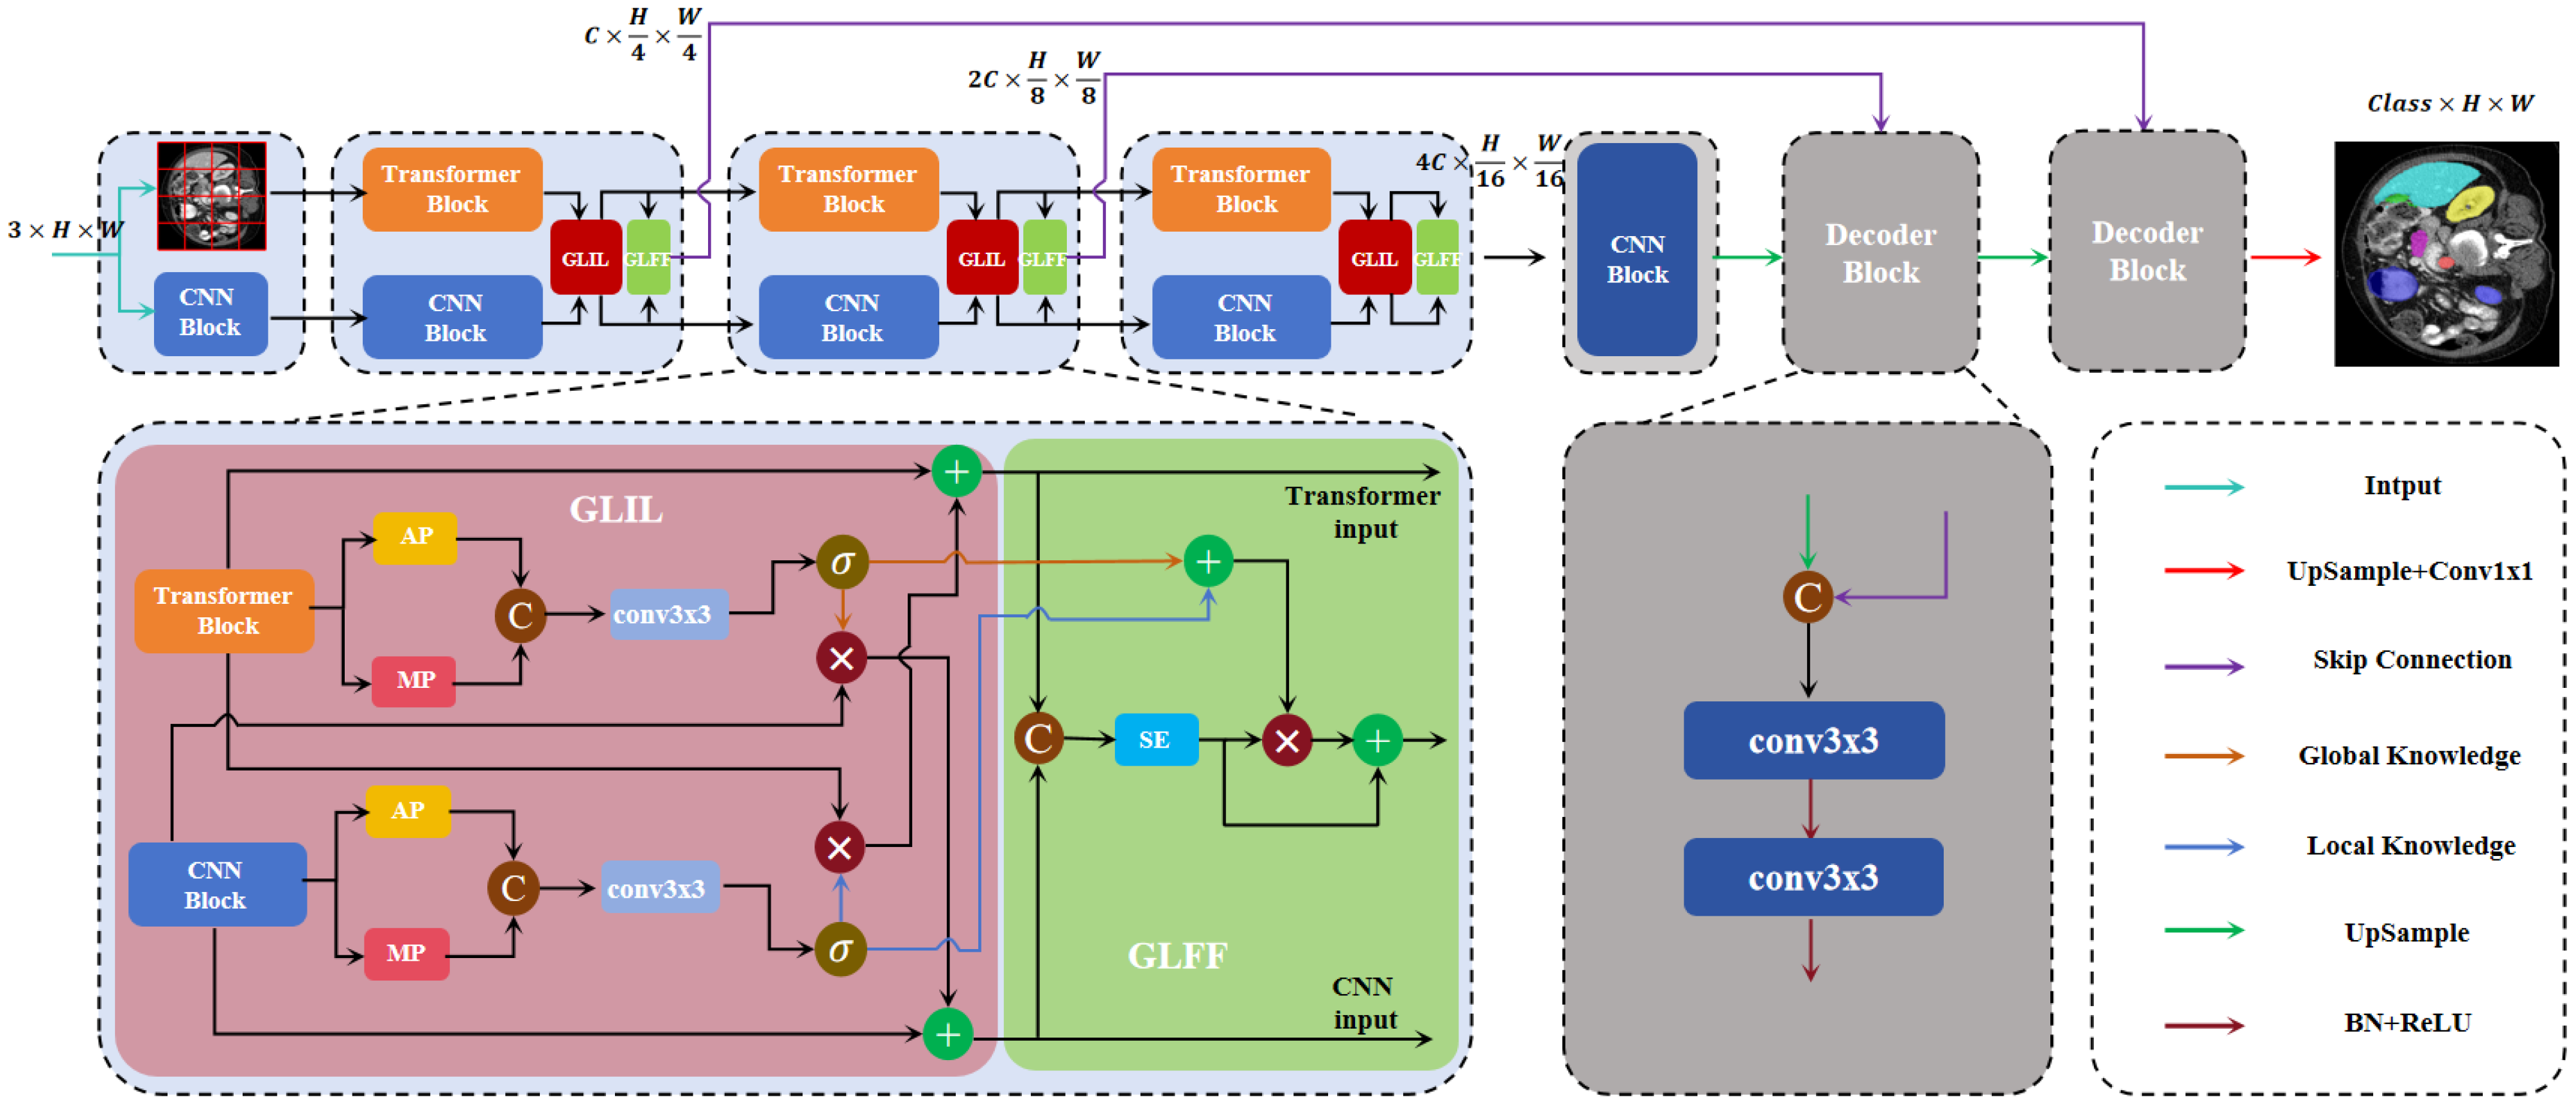

- The introduction of a novel network, DEFI-Net, notably enhancing the MIS performance through Transformer–CNN interactive learning. This interaction is facilitated by the GLIL module. The GLIL module consists of two parallel spatial attention modules: one module extracts global semantic information from the features of the Transformer encoder while the other captures local detail information from the features of the CNN encoder. Effective interaction between the two encoders is achieved by using the global semantic information to weight the features from the CNN encoder and refining the features from the Transformer encoder with local detail information.

- The development of a GLFF module that utilizes the global semantic information and local detail information produced by the GLIL module to integrate features from both the Transformer and CNN encoders. The GLFF module concatenates the features from the two encoders and employs a channel attention mechanism to enhance relevant channel features while suppressing less significant ones. The global semantic and local detail information from the GLIL module is then used to weight the concatenated features, resulting in a more precise feature representation.

3.1. Transformer–CNN Dual-Encoder

3.2. Global–Local Interaction Learning Module

3.3. Global–Local Feature Fusion Module